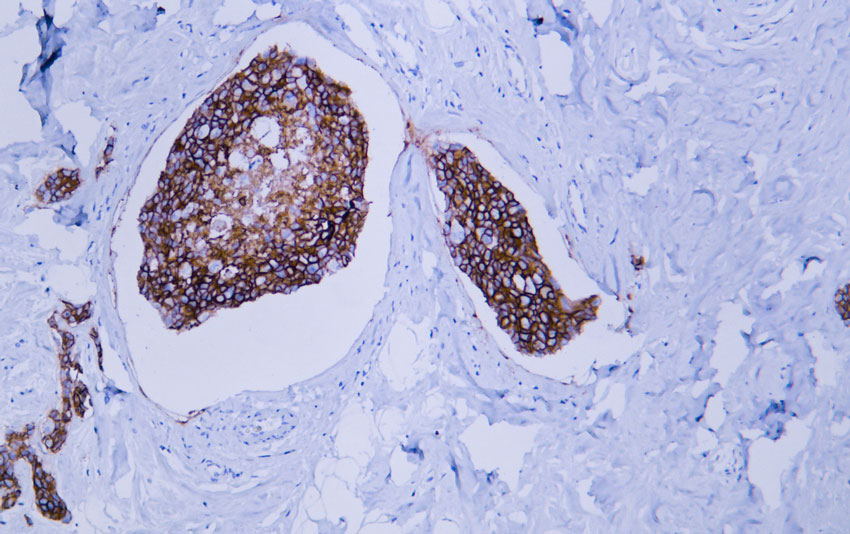

HER2 (ABT008) Mouse mAb

IHC, ELISA

137kD (Calculated) 180kD (Observed)